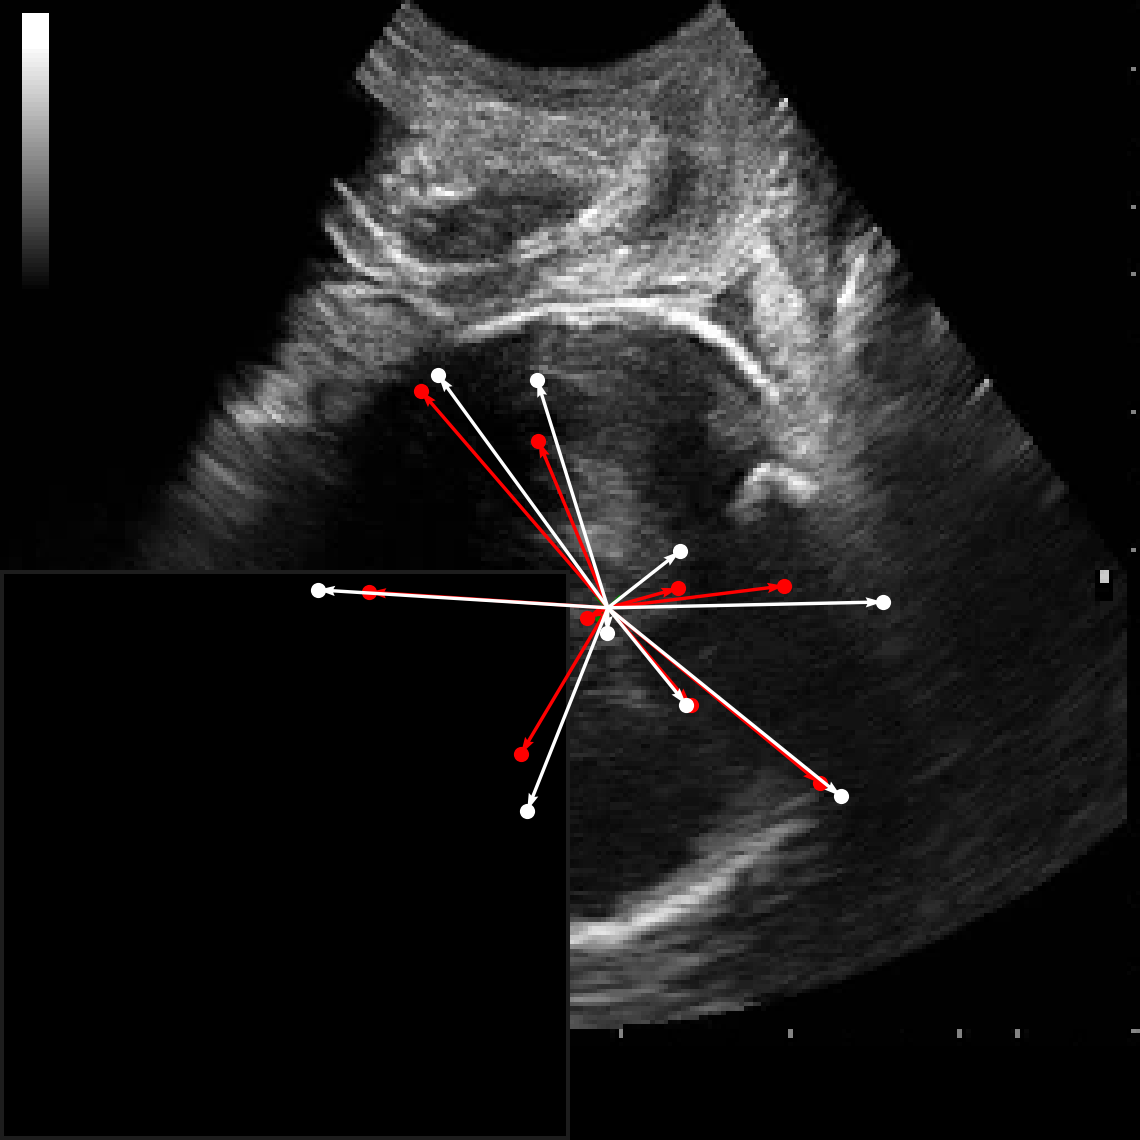

In practical clinical settings, medical images are often incomplete or degraded due to occlusions, artifacts, or limited fields-of-view. Therefore, a reliable segmentation model must be robust to missing spatial context and capable of inferring anatomical structures from partially observed inputs. To evaluate this critical property, we conducted a masking experiment using the FH-PS-AoP dataset. In this experiment, we systematically removed one quadrant from the input image, top-left, top-right, bottom-left, or bottom-right, and evaluated the performance of DAUNet compared to the baseline UNet.

Figure 7 presents a comprehensive visual comparison of the predicted offset maps and segmentation masks under each masking condition. The first column shows the original (unmasked) input along with its corresponding predictions, while subsequent columns depict the results for each of the masked quadrants.

DAUNet demonstrates markedly higher resilience to missing context compared to UNet. Its predicted offset maps remain dense and structured, with vectors that preserve anatomical directionality even when significant regions of the input are absent. This behavior reflects DAUNet’s ability to infer context from the remaining visual cues. In contrast, UNet exhibits sparse or disoriented offsets in the masked scenarios, indicating reduced spatial awareness and compromised localization.

To better understand this phenomenon, we analyzed the receptive fields of both models. For a representative pixel, we visualized its corresponding receptive area contributing to the output. In UNet, the receptive field is fixed and grid-constrained (refer to second row of Figure 7), making it sensitive to occlusions. On the other hand, DAUNet leverages deformable convolutions to dynamically adjust its receptive field based on the visible content. This adaptability is evident in the red and white arrows in the fourth column of Figure 7, where DAUNet modifies its offset patterns to account for the masked input.

The segmentation masks in third and fourth rows of Figure 7, further substantiate these findings. DAUNet consistently produces anatomically plausible segmentations of both the fetal head (green) and pubic symphysis (red), with minimal degradation even under 25% missing input. The output contours remain smooth, accurate, and well-aligned with ground truth boundaries. In contrast, UNet’s performance deteriorates noticeably, with fragmented or distorted segmentations, especially around the fetal head, as indicated by white arrows in the figure.

These results highlight the efficacy of DAUNet’s architectural innovations. The combination of deformable convolution and SimAM attention allows the model to effectively reason over the visible context and compensate for spatial omissions. This robustness to incomplete inputs makes DAUNet well-suited for deployment in real-world medical environments, where noise, occlusions, and partial data are common challenges.